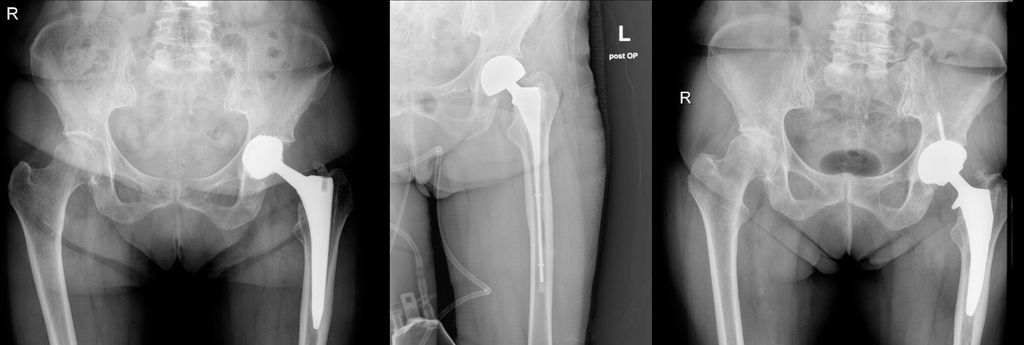

An unserer Abteilung wurde in den letzten 4 Jahren in 13 Fällen ein Downsizing durchgeführt. Gründe für die Revision waren 6 aseptische Lockerungen und 7 periprothetische Infektionen. Es bestanden Typ-II- und Typ-III-Defekte. Abbildung 1 und 2 zeigen zwei Fallbeispiele mit unterschiedlichen Defekttypen. Von den 13 Fällen musste einer aufgrund eines Frühinfektes revidiert werden. Es traten innerhalb von 4 Jahren keine schaftbezogenen Komplikationen auf.

Abb. 2: Downsizing nach aseptischer Lockerung bei einem Typ-III-A-Defekt nach Paprosky